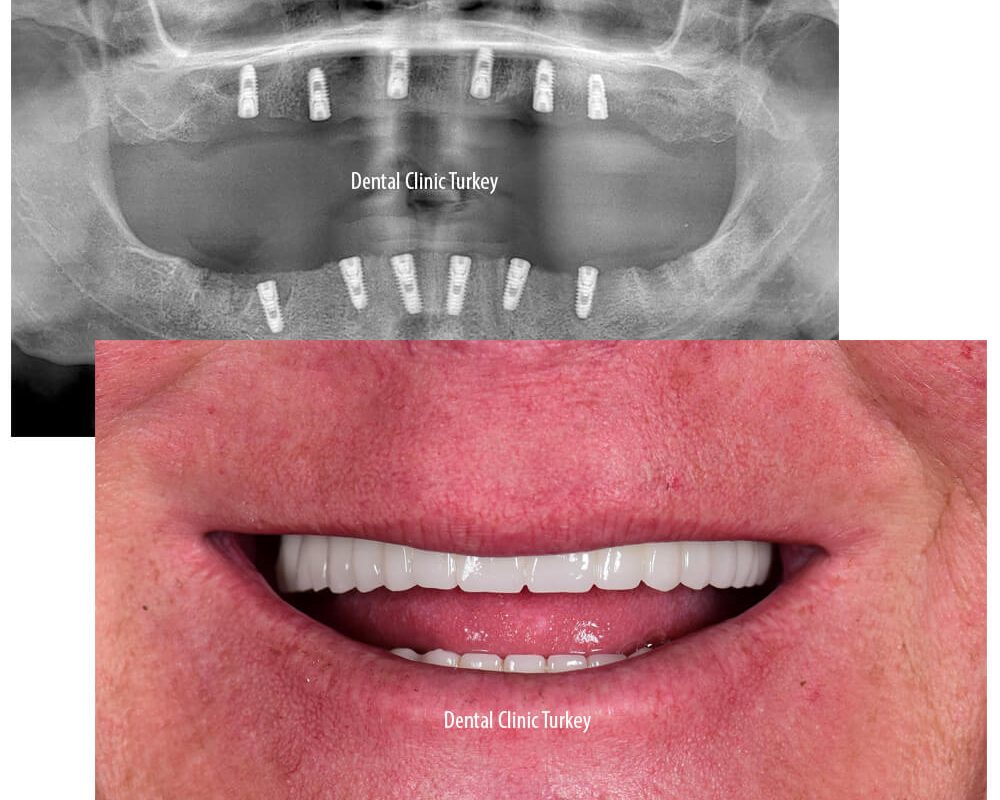

It is taken to provide a general view of dental and jaw health. This type of X-ray can view all of the teeth and bones in the jaw and reveal conditions such as gums, braces, implants, sinus cavities, and missing teeth. The dentist can use these images to plan treatment or evaluate current treatment. In addition, panoramic x-rays can be taken to follow up the teeth and jaw problems determined by the

Implant planning in total edentulism, in order to make implant supported fixed teeth, during the treatment planning, it must be determined in advance what the teeth will look like at the end of the treatment. It is possible to have enough information on this subject with the records taken from the patient, the diagnostic models obtained and the wax models to be made on them.